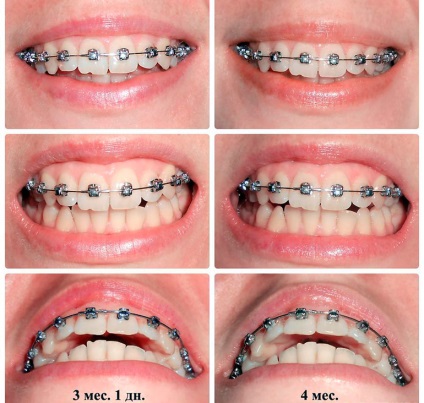

Ezen az oldalon a fotó: zárójelek előtt és után viselése a megjelenés után fogszabályozó fogszabályozó, a fogak előtt és után zárójelben, nadrágtartó, és a fotók másokkal.

A több kép előtt és után viselése a zárójelek azt mutatják, hogy a hatékonysága fogak összehangolás és problémák megszüntetése után. A legtöbb betegnél az eredmény látható néhány hét után.

Nadrágtartók előtti és utáni képek

A fogak fogszabályozó előtti és utáni képek

Összehangolása fogak fogszabályozó előtti és utáni képek

Fényképek előtt és után fogszabályozó viselése